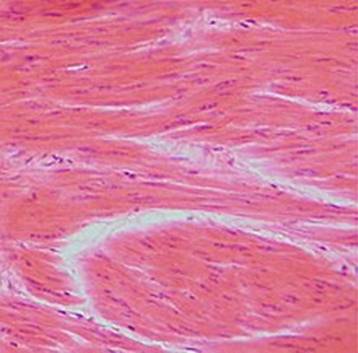

心筋の顕微解剖

上記の通り心筋は横紋筋であるので光学顕微鏡下でも横紋を認める。低倍率では網状構造がよく見える。まれに細胞辺縁に黄褐色の顆粒構造を認めるが、これは心筋が安定組織であるために生成され排泄されない老廃物、いわゆるリポフスチン顆粒である。